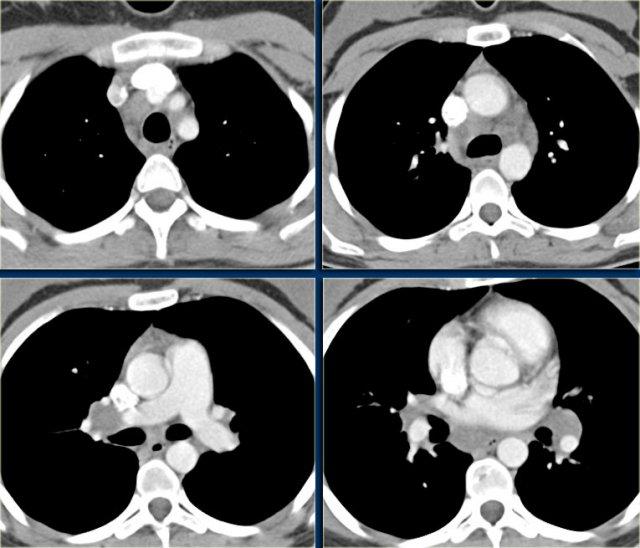

Các hình ảnh cho thấy u tuyến ức ở bên trái và ung thư biểu mô ở bên phải.

Ung thư biểu mô tuyến ức đã xâm lấn tĩnh mạch chủ trên (mũi tên).